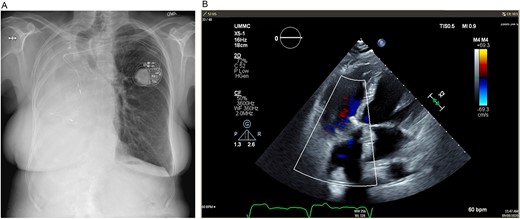

(A) Postoperative posteroanterior view chest X-ray. (B) Postoperative transesophageal echocardiogram with doppler showing a well-seated bioprosthetic valve in the tricuspid position with a mean gradient of 4 mmHg and no measurable insufficiency.